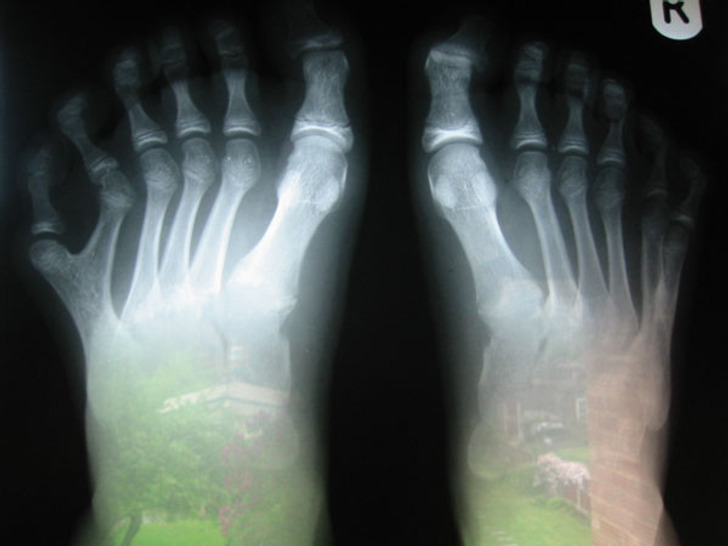

7. Born with an extra toe on each foot

Illustration de l'article : 18 photos of unusual physical traits and natural wonders

© cadex / Reddit